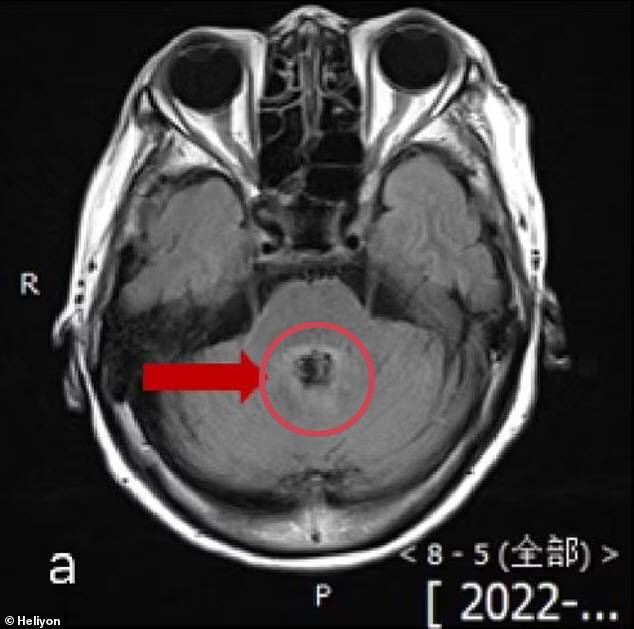

뇌 스캔 검사 결과를 본 의사들은 그녀가 뇌종양을 앓고 있다고 생각했다.

하지만 체액 검사 결과, 뇌로 퍼져 환자 10명 중 9명을 사망에 이르게 하는 단세포 생물인 '발라무티아 만드릴라리스'에 감염된 것으로 나타났다.